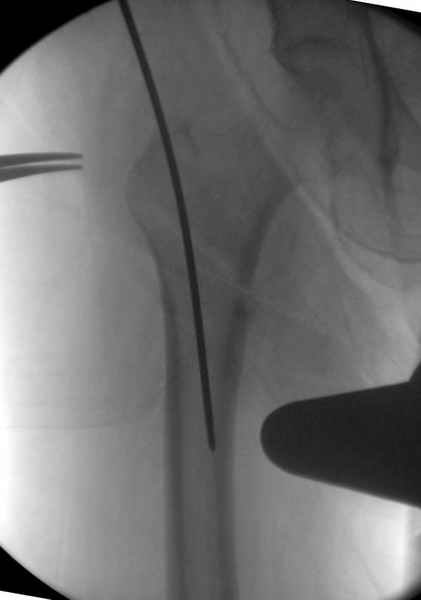

На этом снимке процесс компрессии нижним болтом.